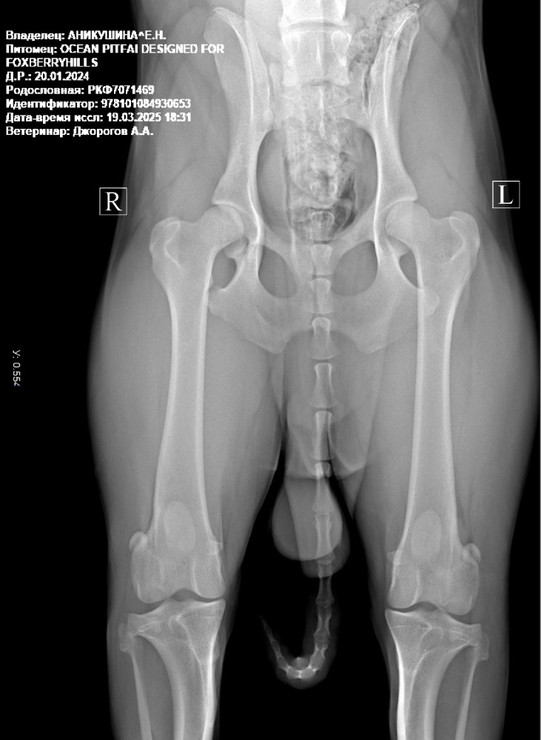

Выраженность клинических симптомов зависит от глубины деструктивных изменений и не во всех случаях дает основание для постановки диагноза. Для уточнения стадий диспластического процесса проводят рентгенологическое обследование больных, которое с высокой степенью информативности позволяет сделать заключение о структурно-функциональном состоянии тазобедренных суставов.

Рентгенографическая диагностика на дисплазию тазобедренного сустава достоверна на 70% в возрасте до одного года, и на 95.4% — до двух лет.

Это делается по общим наркозом, вытягивая собаку на столе, при этом растягивая и выворачивая внутрь ее задние ноги. Эту процедуру невозможно сделать без наркоза. Даже самые послушные собаки инстинктивно начинают сопротивляться, когда им тянут и выворачивают ноги, для этого и используется наркоз, чтобы мышцы были полностью расслаблены. Также как у человека, у собак существует риск при даче наркоза, но до сих пор ни одно животное не погибло при проверке на дисплазию.